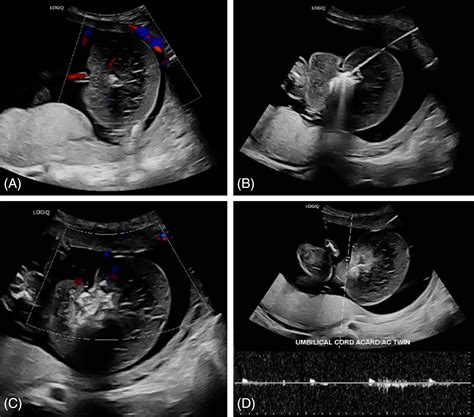

Early diagnosis of TRAP sequence is crucial for managing the condition effectively. Ultrasound examinations are the primary diagnostic tool, typically performed between 10 and 14 weeks of gestation. Key indicators of TRAP sequence include:

• Absence of a heartbeat in the acardiac twin.

• Reverse blood flow from the pump twin to the acardiac twin.

• Abnormal development of the acardiac twin, often characterized by a lack of a functional heart and other organ malformations.

Doppler ultrasound is particularly useful in visualizing the abnormal blood flow patterns characteristic of TRAP sequence. Magnetic Resonance Imaging (MRI) may also be used to provide a more detailed assessment of the twins' anatomy and the extent of the condition.